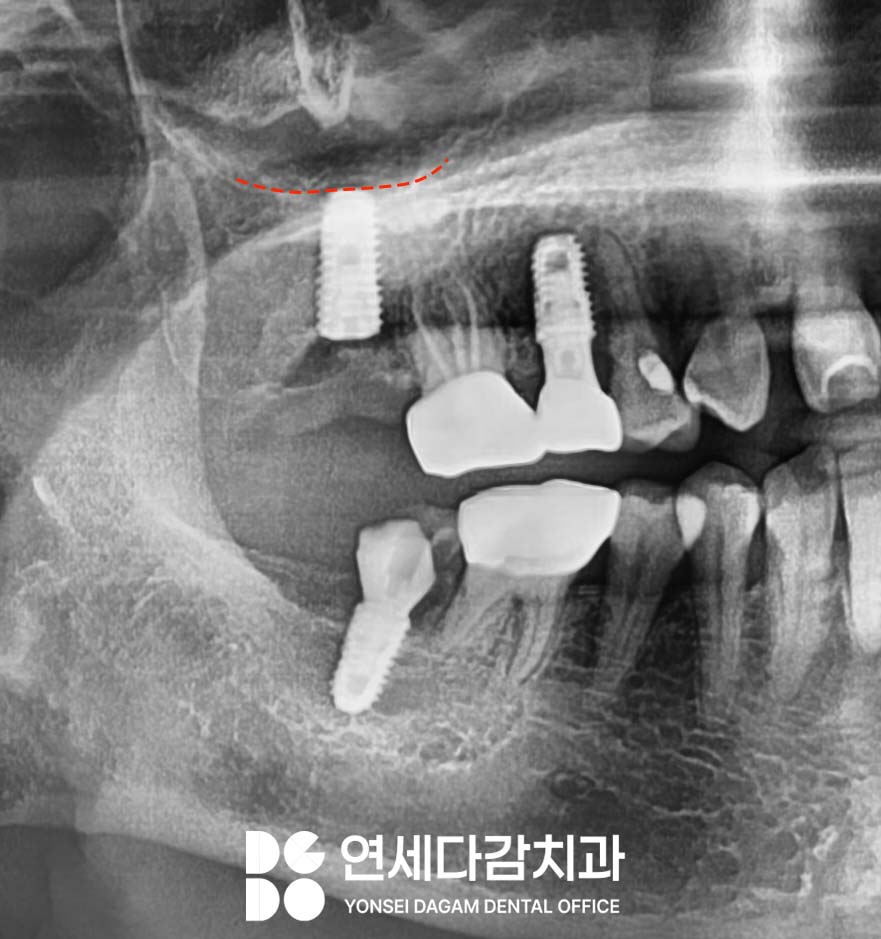

가락동 치과 에서 표시한

상악 어금니 부위는

임상적으로 임플란트 실패율이

상대적으로 높은 곳으로 알려져 있습니다.

이는 해당 부위의 골밀도가

다른 부위에 비해 낮고,

특히 끝에 위치한 어금니는

저작 시 다른 부위보다

훨씬 큰 힘을 받기 때문입니다.

그러나 이 부위가 뼈의 밀도가 낮고

상대적으로 어려운 곳이라고 하더라도,

두 번의 연속적인 수술 실패가

일어날 정도로 극단적으로

어려운 곳은 아닙니다.

따라서 다른 원인이

있을 것으로 판단했습니다.

그러나 가락동 치과 에서 앞서

히스토리 설명드린 것처럼

이미 두꺼운 고정체로도

실패한 히스토리가 있었기 때문에,

다른 접근 방식이 필요했습니다.

골밀도가 전반적으로 낮다는

점을 고려하여,

상악동 저부에 위치한 피질골을

적극 활용하는 전략을 수립했습니다.